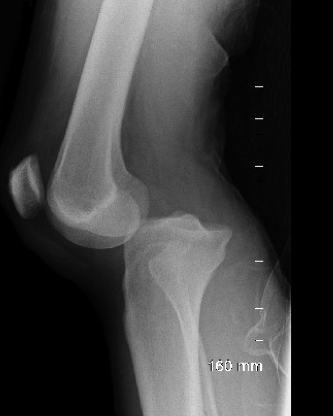

The vascular injury that can arise from this injury.

What is a popliteal artery injury?

Salter-Harris classification for this fracture.

What is a Salter Harris IV fracture?